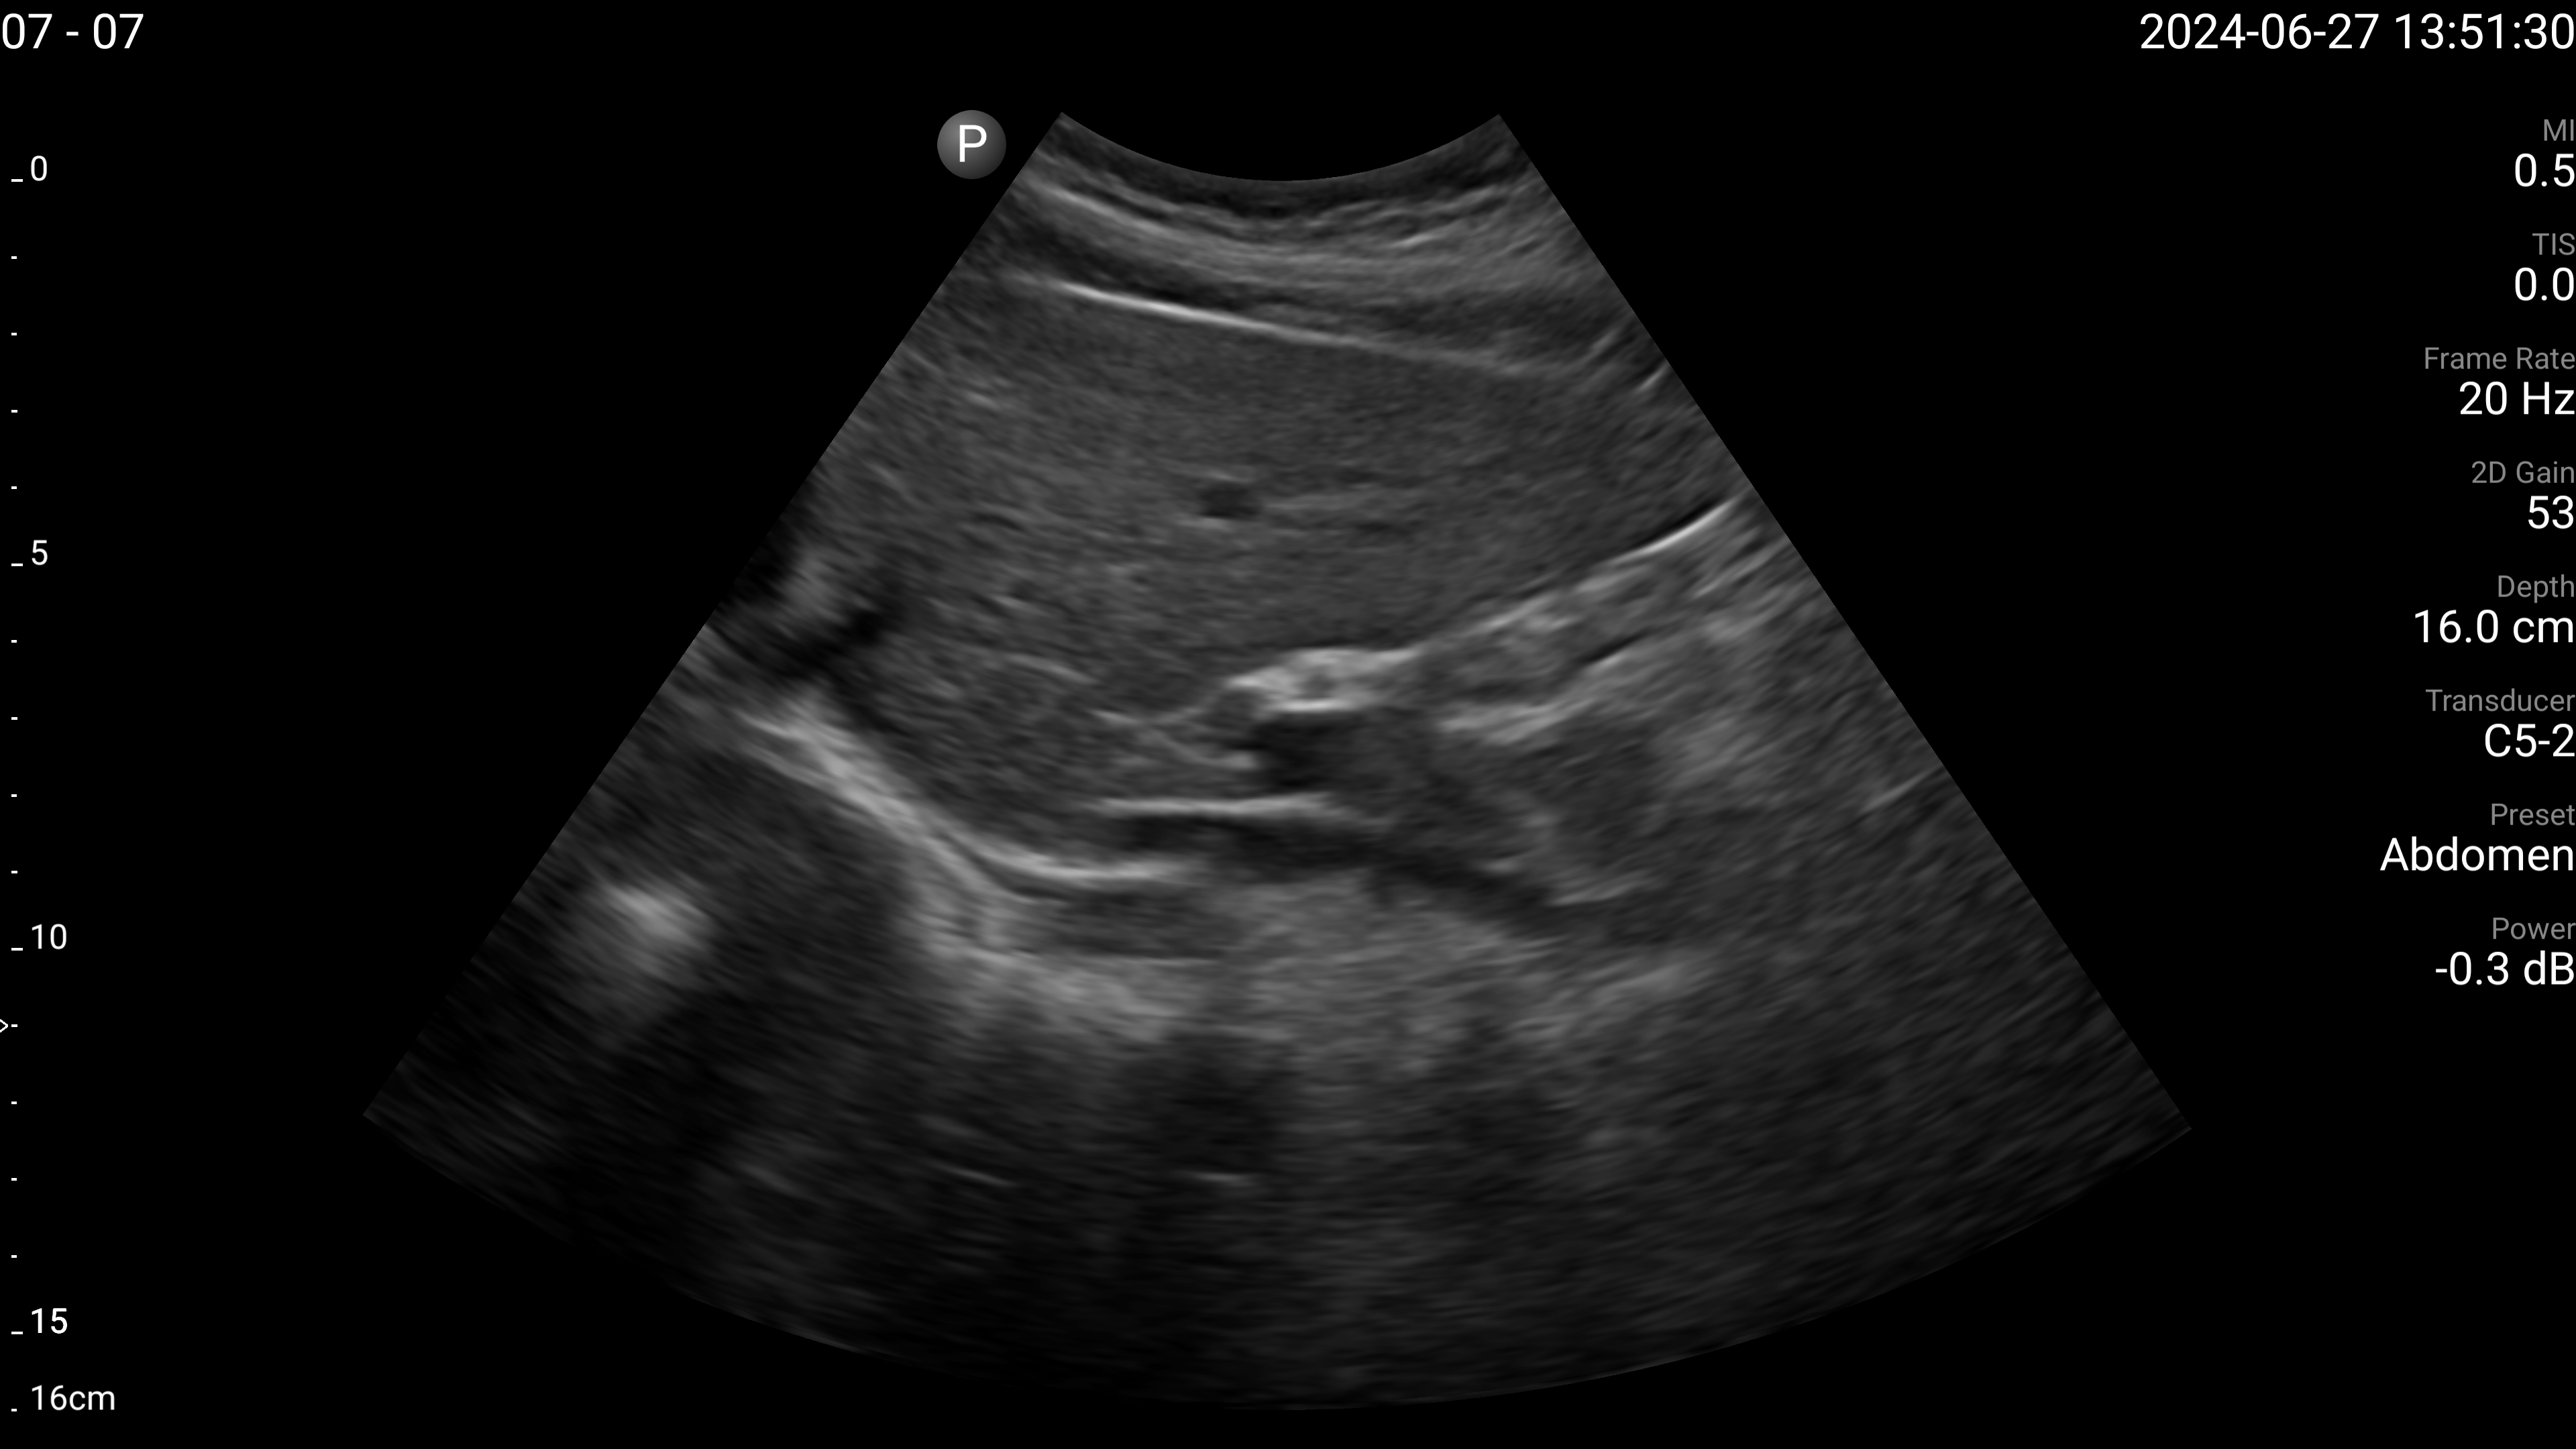

Refer to caption

(d) Left lobe of liver - transverse.

Figure 4: Examples of the target US images acquired by the sonographers using the human teleoperation system.

The sonographers completed 11 abdominal US scans, each with 5 target images and measurements for a total of 55 images. An example image of each of the targets acquired during these tests is shown in Fig. 4. After completing the scans, two radiologists scored the images based on quality, including identifying targets that could not be seen or were not captured (which were given a score of 0). The distribution of these scores is illustrated in Fig. 5. The first radiologist identified 4 out of the 55 targets as not visible, while the second radiologist identified 6 out of 55 as not visible. Combined, this accounted for 7 unique targets that at least one radiologist considered missing. Of these missing targets, three were not captured due to large amounts of bowel gas and body habitus while one was seen but the sonographer did not capture and save the image. When excluding all the missing targets, the images obtained a mean score of 4.28±0.95plus-or-minus4.280.954.28\pm 0.95 out of 5 and 91.7% of the images were scored 3 or higher by both radiologists. A score of 3 or higher indicated the image quality was sufficient for basic image interpretation. 31.3% of the images were scored 5 by both radiologists, indicating the image quality was good and meaningful image interpretation was easy.